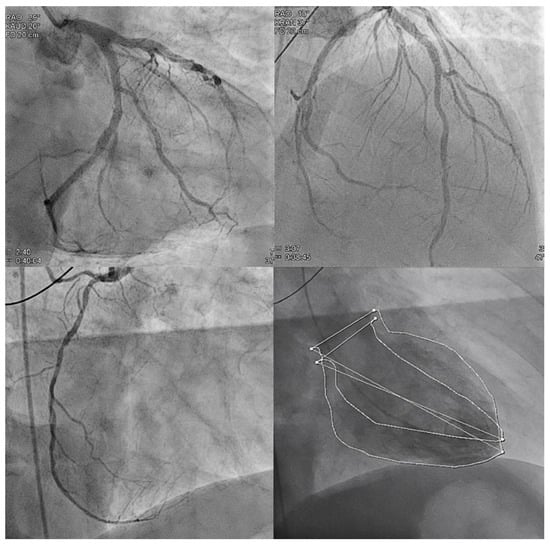

Despite the premature discontinuation of DAPT, the DES in the proximal/mid LAD and the BMS in the dominant LCX were both patent. The right coronary artery (RCA) was non-dominant, diffusely sclerotic and perfused to the distal periphery. The left ventriculography (LVG) showed a normal left ventricular function without regional wall motion abnormalities (RWMA) (Figure 3).

One of the most common causes of OHCA due to VF in adults is an ACS. According to international guidelines [3], in the presence of ST-segment elevation in the 12-lead ECG after ROSC, a coronary angiography has to be performed as soon as possible. The coronary angiogram in our case showed that both stents in the LAD and LCX were patent. The non-dominant RCA was diffusely but moderately diseased (Figure 3). At admission, the previous angiograms were not available for comparison, which made the diagnosis of iRVMI challenging. Due to the discontinuation of antiplatelet therapy, a transient late stent thrombosis was initially considered a possible cause.

Figure 3. Angiograms of the left and right coronary arteries showing patent vessels and stents. Bottom left ventriculography showing normal left ventricular ejection fraction without regional wall motion abnormalities.